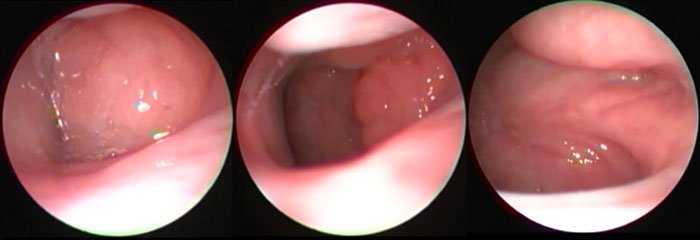

Geniz etini, endoskoplarla yaptığımız rutin kulak burun boğaz muayenesinde, çoğu kez doğrudan gözle görerek belirleyebiliyoruz. Günümüzde bu konuya eğilmiş merkezlerde, çocuklar için geliştirilmiş ince pediatrik endoskoplar kullanarak burun boşluğunu ve arkasında bulunan geniz etininin boyutlarını kaydetmek olanaklı. Deneyimli ellerde çocuğa önemli bir sıkıntı vermeden yapılabilen bu muayene ile geniz etinin yol açtığı diğer sorunları (örneğin kulak sıvısı) da beraberinde değerlendirebiliyoruz.

Geniz eti hangi teknikle alınırsa alınsın, önemli olan gelecekte sorunların tekrarlamasına yol açabilecek geniz eti dokusunun geride kalıp kalmadığıdır. Günümüzde bu konudaki en önemli gelişme, geride doku kalıp kalmadığını gözleyebilmemizi sağlayan, çocuklar için özel olarak geliştirilmiş ince pediatrik endoskoplardır. Aynı rutin muayenede olduğu gibi, ameliyat sırasında da yapılan endoskopi sayesinde, geniz etinin tamamının alınıp alınmadığı böylelikle kontrol edilmiş olur, kanama kontrolü görerek yapılabilir ve hastalığın tekrarlama olasılığı azalır.